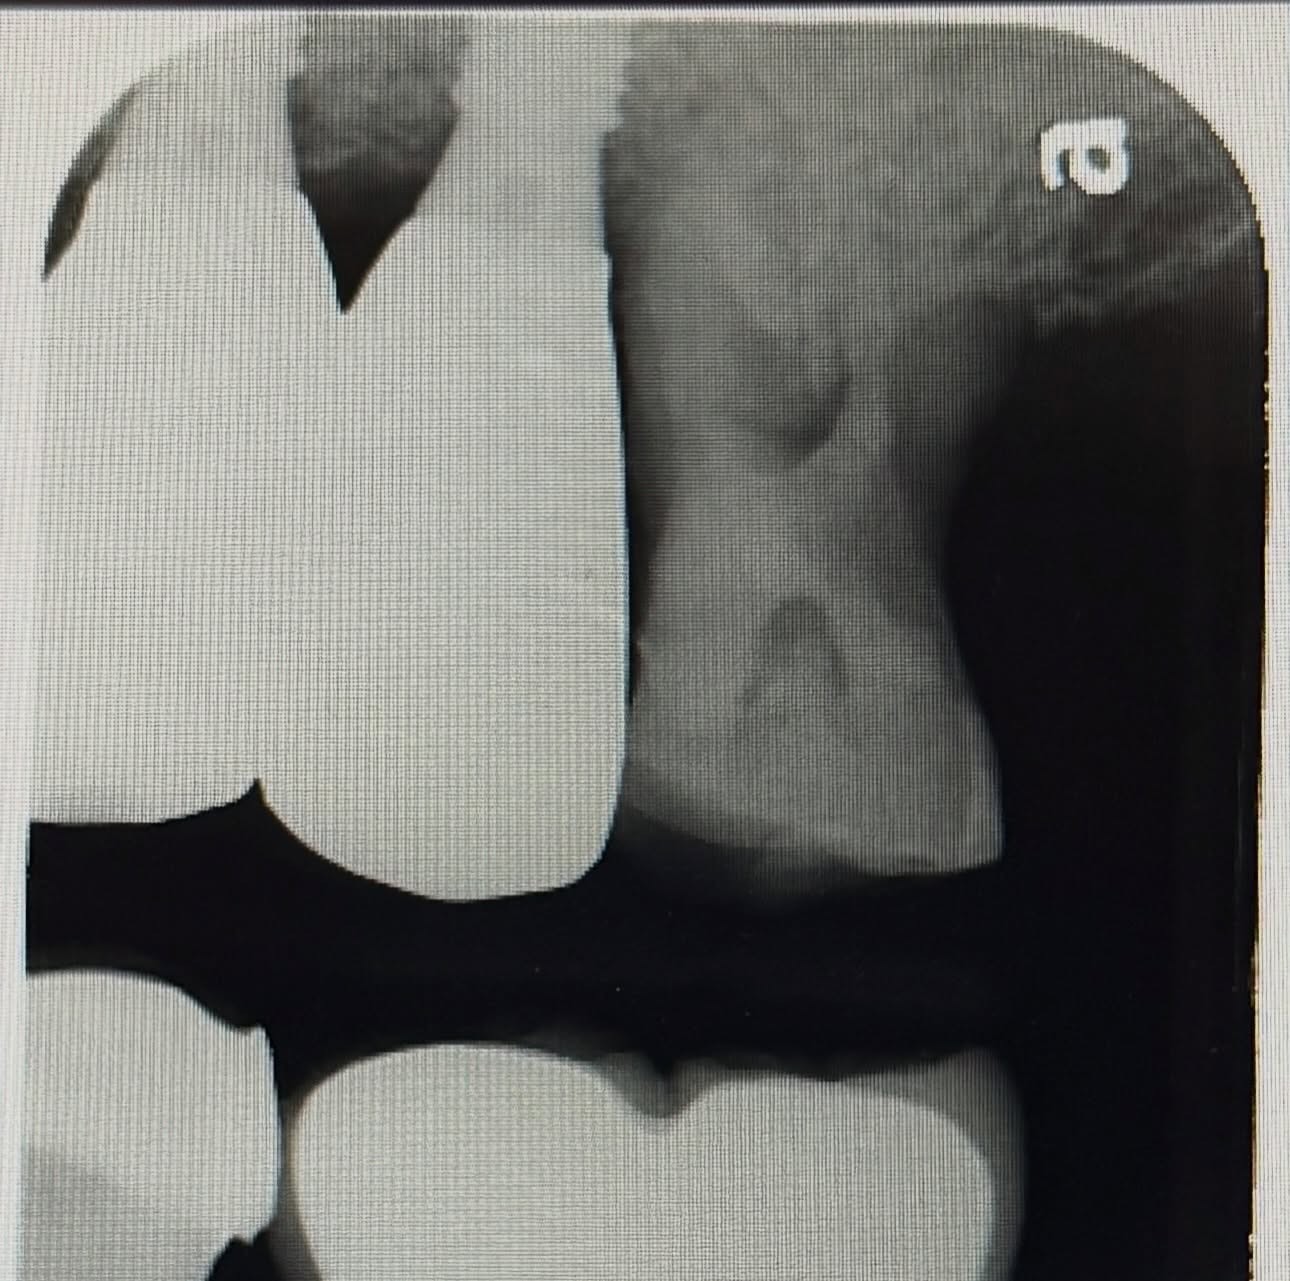

在牙周探測的部分只有單點較深的牙周囊袋,棉捲咬合測試則咬時痛;放開則不痛,另外拍攝X光片時發現有異狀-單側骨缺損(骨頭一般白一邊黑)。

當聽到患者說咬到食物會痛,臨床上檢查發現單點有較深的牙周囊袋(意味著細菌從此處入侵),X光檢查發現像圖片呈現的單側骨頭缺損,此牙就可能是牙根裂掉了。簡院長推測此牙因根管治療過,雖經牙套保護起來,但還是承受不住咬合壓力導致裂掉。令院長感到訝異的是,初診的Y小姐非常相信院長的診斷,即使院長請Y小姐可以問問第二位牙醫師來確認診斷,Y小姐仍接受百謙院長的治療方式—移除患齒🦷,做齒槽骨保存術,以利日後植牙。謝謝第一次來看牙的Y小姐這麽相信君悅和簡院長。像許多醫師一樣,百謙院長和君悅的醫師們會很仔細的診察,找出問題點,因為正確的診斷才能做出真正的治療,這也是百謙院長有時會請患者看第二個診所的原因,減少患者被誤判的可能性。

右上圖可以看出骨粉填充的很緻密,x光照出幾乎無黑影👍🏻等待半年骨頭長好後就可以進行植牙手術。